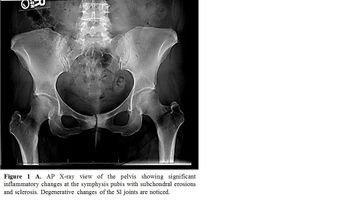

Inflammatory bowel disease patients can be afflicted by various forms of arthritis from peripheral arthritis to ankylosing spondylitis and symmetrical polyarthritis. In this slideshow, we address identification, diagnosis and treatment for these complex cases.